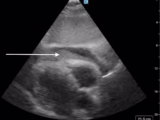

Utilizing POCUS for the Identification and Management of PICC Line-Associated Cardiac Tamponade

Pedro Jose Cruz Guzman; Karen Lidsky; William Hanna - This case report describes a 5-month-old ex-premature infant who developed cardiac tamponade associated with PICC line malposition. Point of care ultrasound (POCUS) was used to diagnose and effectively manage the condition peri-arrest via emergent pericardiocentesis.